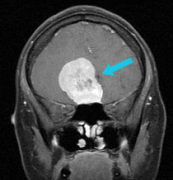

48岁的赵先生,因为突发癫痫就医,家人带其MRI检查后发现大脑左额镰旁有肿瘤占位,病理结果是 脑膜瘤 。 两次手术治疗后依然恶化 由于赵先生才48岁,为了以后健康的生活,赵先生...

头痛是生活中常见的症状,大多人都出现过头痛、头晕症状,但一般吃点药或过一段时间就好了。而51岁的李女士(化名),却近来因为莫名头痛,在医院核磁共振查出 右侧颞部脑膜...